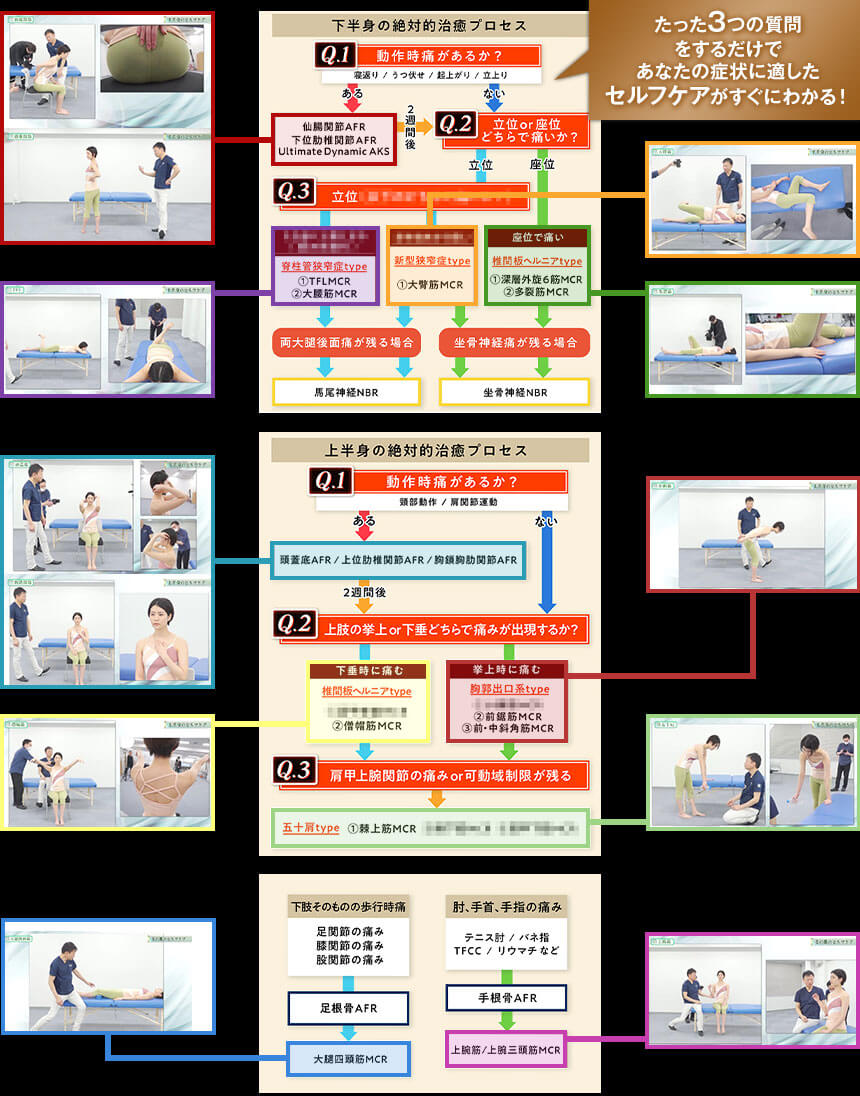

これが、AKS療法®の絶対的治癒プロセスです。この図は患者さんが来た時の問診時に使えるフローチャートになっており、あなたは上半身、下半身それぞれに対応する3つの質問「Final 3 Qestion」を患者さんに聞き、絶対的治癒プロセスに則ってチャートを進むだけで、原因が明確になり、アプローチする手技が明確になるのです。

- ①フローチャートに沿って誰でも出来る3つの質問をする

⇒医師も分からない真の症状の原因が浮き彫りに! - ②チャートから導き出された手技をやるだけ

この絶対的治癒プロセスを使えば、たとえあなたが解剖学をまったく知らない素人だとしても、患者さんの痛みの真の原因が分かるようになるので、原因が分からずに全身を揉んでみたり、治療に悩んだり不安になることがなくなるのです。

つまり、この絶対的治癒プロセスはゴッドハンドと同じ診立てや問診、治療計画を立てるためのカンニングペーパーのようなものであり、手技の使い方をナビゲートしてくれるものです。

この、たった3つの質問で症状の根本原因を明らかにし、患者さんの未来予測までできるようになる絶対的治癒プロセスと手術宣告された重症患者さんでも回復に導く手技の両方が揃っている最強の治療法が「AKS療法®-Final-」であり、“素人でも重症患者さんを回復に導ける”と自信を持っておススメできるのです。

殺到するほど効果が高い - たった3つの質問をするだけで、

根本原因が明確になる - 手術宣告された “重症患者ほど”